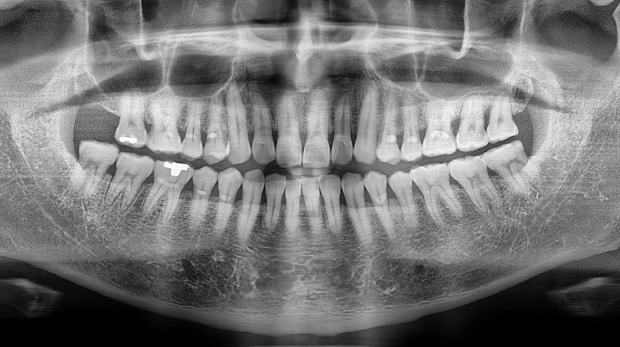

박** 환자분 (오른쪽 상하악 사랑니 동시 발치 케이스)

상악의 경우 단순매복으로 발치 및 동시에 하악 잇몸뼈에

깊게 박혀잇는 고난이도 케이스, 잇몸절개 후 치아 분리하여

발치하였으며